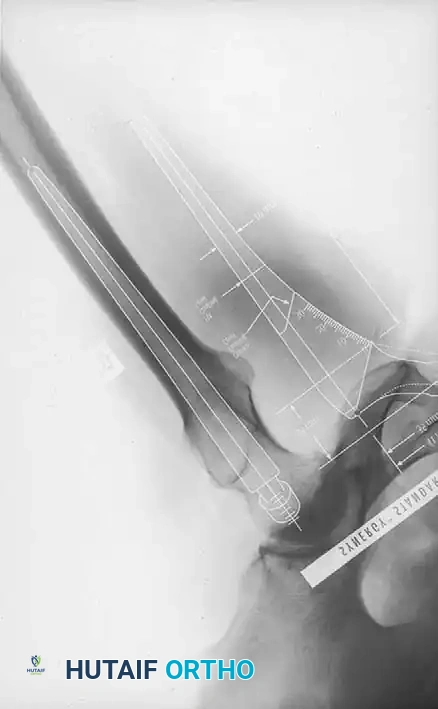

The foundation of a successful Total Hip Arthroplasty (THA) is laid long before the first incision. Meticulous preoperative templating is mandatory to anticipate the optimal size of the components, restore the anatomic center of rotation, equalize leg lengths, and re-establish femoral offset. Failure to accurately template can lead to intraoperative compromises, resulting in altered biomechanics, instability, or accelerated polyethylene wear.

Standard preoperative radiographs must include an anteroposterior (AP) view of the pelvis centered over the pubic symphysis (with the hips internally rotated 15 degrees to profile the femoral neck) and a lateral view of the affected hip.

1. Determine Leg Length Discrepancy: A horizontal reference line is drawn across the bottom of the radiographic teardrops or the ischial tuberosities. The difference in the perpendicular distance from this line to a reproducible landmark on the proximal femur (usually the lesser trochanter) approximates the amount of limb shortening.

2. Acetabular Templating: The acetabular template is positioned at a 40- to 45-degree angle of inclination. It should correspond closely to the subchondral bone plate, ensuring adequate lateral coverage and medialization to the true floor (ilioischial line). The new center of rotation is marked.

3. Femoral Templating: The femoral template that most closely matches the proximal and distal size and contour of the femoral metaphysis and diaphysis is selected.

4. Neck Length and Offset: The neck length and offset are estimated to restore the abductor moment arm. The anticipated level of the femoral neck resection is marked relative to the lesser trochanter.

Fig. 7-40 Templating of radiographs for preoperative planning. A, Line drawn across the bottom of the pelvis to assess limb shortening. B, Acetabular template placed to mark the new center of rotation. C, Femoral template matching the metaphysis. D, Neck length and offset estimation.

Advanced templating systems, such as the Synergy system, allow for precise calculation of standard versus high-offset stems to fine-tune soft-tissue tension.

Intraoperative and postoperative radiographs should confirm that the completed arthroplasty corresponds to the preoperative plan, with implants properly sized and leg length/offset correctly restored.